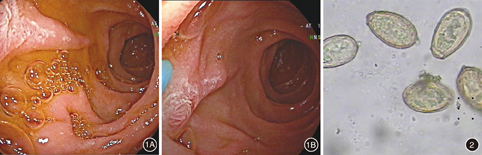

患者男,60岁,因"腹胀1个月,纳差7 d,发热1 d"入院。患者近1个月出现较明显腹胀,逐渐食欲下降,伴有餐后恶心,1 d前突然发热,体温最高达到39℃,不伴明显畏寒、寒战,无腹痛,无呕吐,无咽痛,无咳嗽、咯痰,无头痛,无肌肉痛,大便如常,尿色稍黄。起病前1个月自制药酒饮服,每天约半斤。近期无外出旅游。近期广州市内较多流感病例,患者家属中暂无感染者。患者有"高脂血症"10余年,无长期服药;无"肝炎、肺结核"等传染病史;无嗜酒史,平素喜欢吃鱼,但不吃鱼生。入院查体:体温39.6℃,心率89次/min,呼吸20次/min,血压142/81 mmHg(1 mmHg=0.133 kPa),神志清晰,体型偏胖,营养良好,皮肤无焦痂、斑丘疹、皮下出血斑点等,全身浅表淋巴结无肿大,巩膜无黄染,无咽喉充血,双侧扁桃体无肿大和渗出,胸廓正常,呼吸运动对称,双肺叩诊音清,双肺呼吸音清,无干湿罗音,心浊音界无扩大,心率89次/min,律齐,无心包摩擦音,各瓣膜区无病理性杂音,腹稍膨隆,未见胃肠型或蠕动波,无腹部静脉显露,全腹软,右上腹有压痛,无反跳痛,无肝区叩痛,墨菲征可疑阳性,移动性浊音阴性,肠鸣音4次/min,双下肢无浮肿,腓肠肌无压痛。血常规:白细胞7.33×109/L,中性粒细胞比率0.646,单核细胞比率0.112,嗜酸性粒细胞比率0。肝功能:ALT 94.0 U/L,AST 98.0 U/L,GGT 85 U/L,TBIL和DBIL正常。C反应蛋白(CRP) 76.0 mg/L,降钙素原(PCT) 2.32 ng/mL。尿常规:尿胆原(+++),尿蛋白(++),24 h尿蛋白0.62 g。粪便常规+隐血(-)。肝炎系列(-),肺炎九项(-),EB病毒抗体(-),TORCH四项(-),肥达氏反应(-),外斐氏反应(-),甲型流感抗原(-),乙型流感抗原(-)。两次血培养(-)。腹部超声:脂肪肝并肝稍大,胆囊内胆汁淤积;脾、胰未见异常声像图;门静脉、肝静脉血流未见异常。腹部CT:轻度脂肪肝,肝脏散在小囊肿;前列腺钙化;胆、胰、脾、双肾、双肾上腺及膀胱未见明显异常。患者入院后予多烯磷脂酰胆碱护肝和观察热型,入院后5 d内均有39℃以上发热,第5天达最高(40 ℃),热型呈弛张热,不排除感染性发热,入院后第3天予左氧氟沙星静脉滴注,第5天联合应用头孢噻肟钠舒巴坦钠静脉滴注,第6天体温迅速下降至正常后未再发热,但仍腹胀、食欲减退。复查血常规:白细胞10.65×109/L,中性粒细胞比率0.261,淋巴细胞比率0.669,嗜酸性粒细胞比率0.010。尿常规:尿蛋白(±)。粪便常规+隐血(-)。CRP 18.8 mg/L。PCT 0.27 ng/mL。肝功能:ALT 97.0 U/L,AST 66.0 U/L,GGT 214 U/L,TBIL和DBIL正常。高度怀疑急性胆管炎,不排除肝吸虫感染,于入院第14天行胃镜引导下十二指肠液引流术(图1),收集A、B、C三管胆汁送实验室查找寄生虫卵,3管肝吸虫卵均为阳性(图2)。建议患者服吡喹酮驱虫治疗。

本病例发热热型呈弛张热,虽然外周血白细胞和中性粒细胞没有升高,但CRP和PCT升高,故倾向感染性发热,经过一系列感染性疾病的排查,并经验性选用抗菌药物后体温迅速下降,支持细菌性感染,需要进一步明确感染部位。患者GGT较ALT和AST升高明显,高度怀疑急性胆管炎,诱因可能与起病前饮酒有关。此外,结合患者平素喜欢吃鱼,虽然反复粪便常规检查虫卵阴性、外周血嗜酸性粒细胞无升高、腹部B超和CT未见肝内外胆管明显异常,仍不排除存在肝吸虫感染造成肝内小胆管堵塞。最终通过胃镜引导下十二指肠液引流术,收集胆汁发现肝吸虫卵而确诊肝吸虫感染。因此,对疑有肝吸虫感染者,应多种检查结合,以期提高本病诊断率,其中胃镜引导下十二指肠液引流术具有定位快速准确、引流方便快捷、不损伤肝内外胆管等优点,适用于反复粪便常规查找虫卵阴性、无ERCP指征又高度怀疑肝内胆管疾病如肝吸虫感染者[7]。